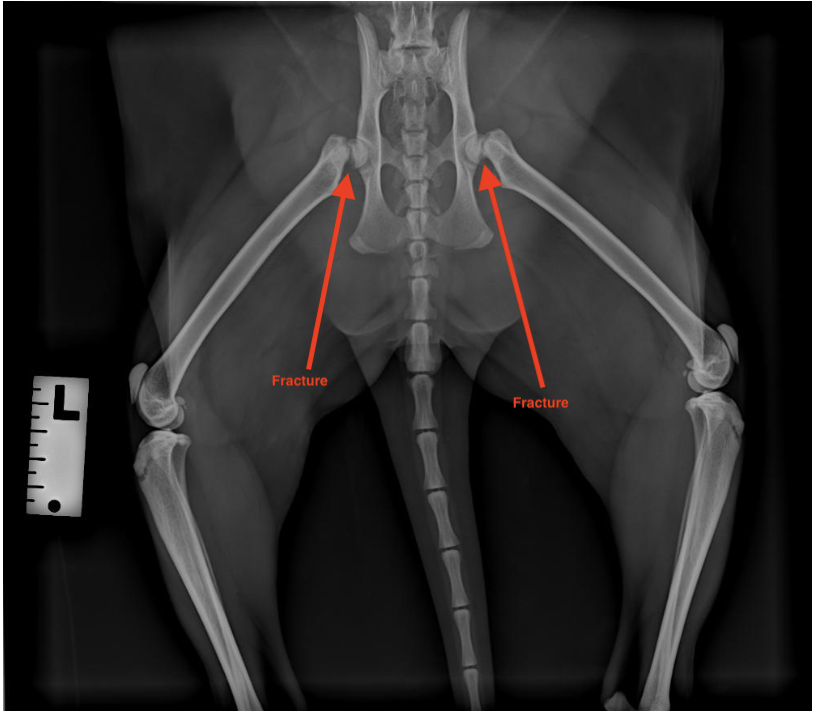

Orthopedic procedures focus on treating injuries and conditions affecting your pet’s bones, joints, and ligaments. These surgeries help restore mobility, reduce pain, and improve your pet’s quality of life. Common orthopedic procedures include fracture repairs, cruciate ligament repairs, patella luxation correction, and femoral head ostectomy (FHO).

Whether your pet has suffered an injury or is experiencing joint-related issues, our expert surgical team provides advanced, affordable orthopedic care to help them move comfortably again. We use the latest techniques to ensure a safe and smooth recovery.